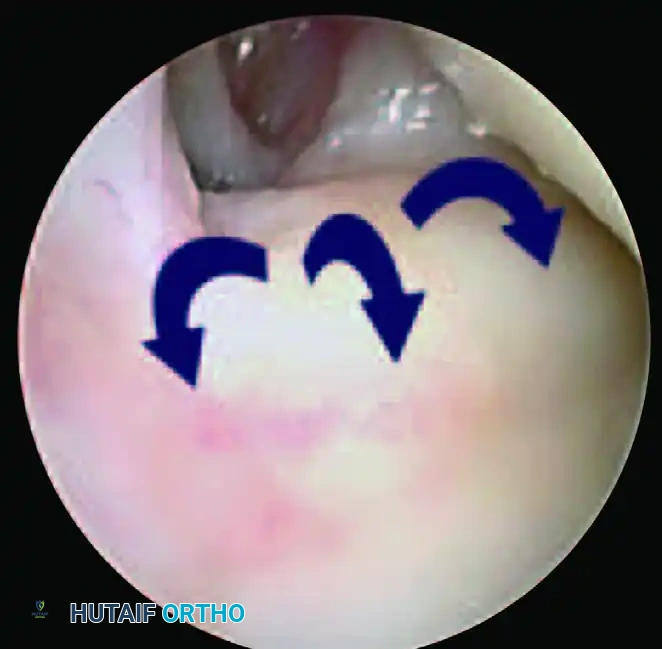

2. The Hook Test:

The probe is inserted into the prestyloid recess to engage the ulnar periphery of the TFCC. The surgeon attempts to pull the complex radially and proximally. If the TFCC can be displaced toward the center of the radiocarpal joint, it signifies a loss of its proximal foveal attachment.

Initial engagement of the probe during the Hook Test in the prestyloid recess.

Positive Hook Test demonstrating abnormal displacement and laxity of the TFCC, confirming a peripheral tear.

According to the Atzei and Luchetti classification, an isolated distal TFCC tear will yield a positive trampoline test but a negative hook test. Conversely, complete or proximal foveal tears will render both tests positive, necessitating foveal reattachment.